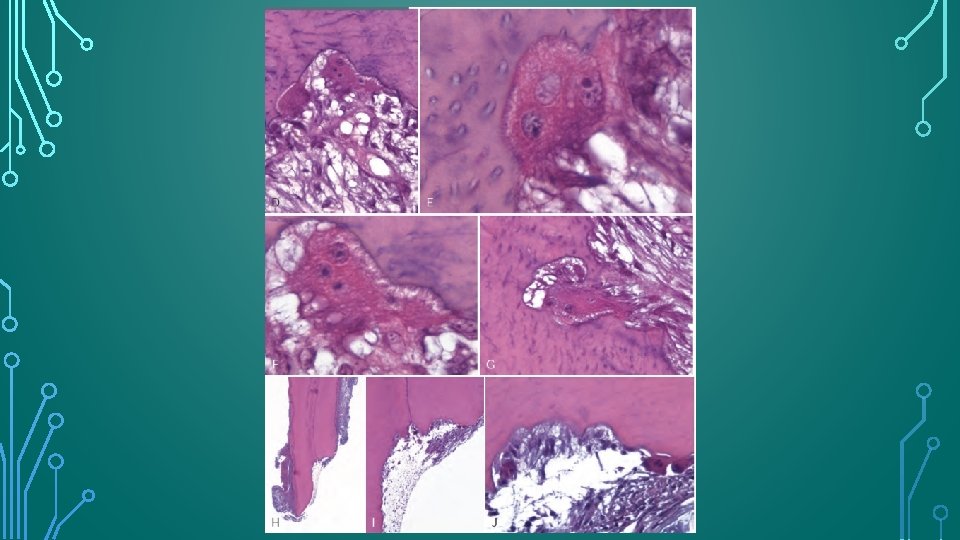

HISTOLOGIC APPEARANCE • Saucer or bowl shaped areas of resorption in both the cementum and dentin, with concomitant inflammation in the adjacent periodontal membrane. • Howship’s lacunae occupied by odontoclasts. • Intense inflammatory reaction in the periodontal membrane consists of a mixed-cell infiltrate that includes plasma cells, lymphocytes, and polymorphonuclear leukocytes in a granulation tissue matrix showing proliferation of capillaries. • EIR can be identified histologically 1 week after experimental replantation of teeth.